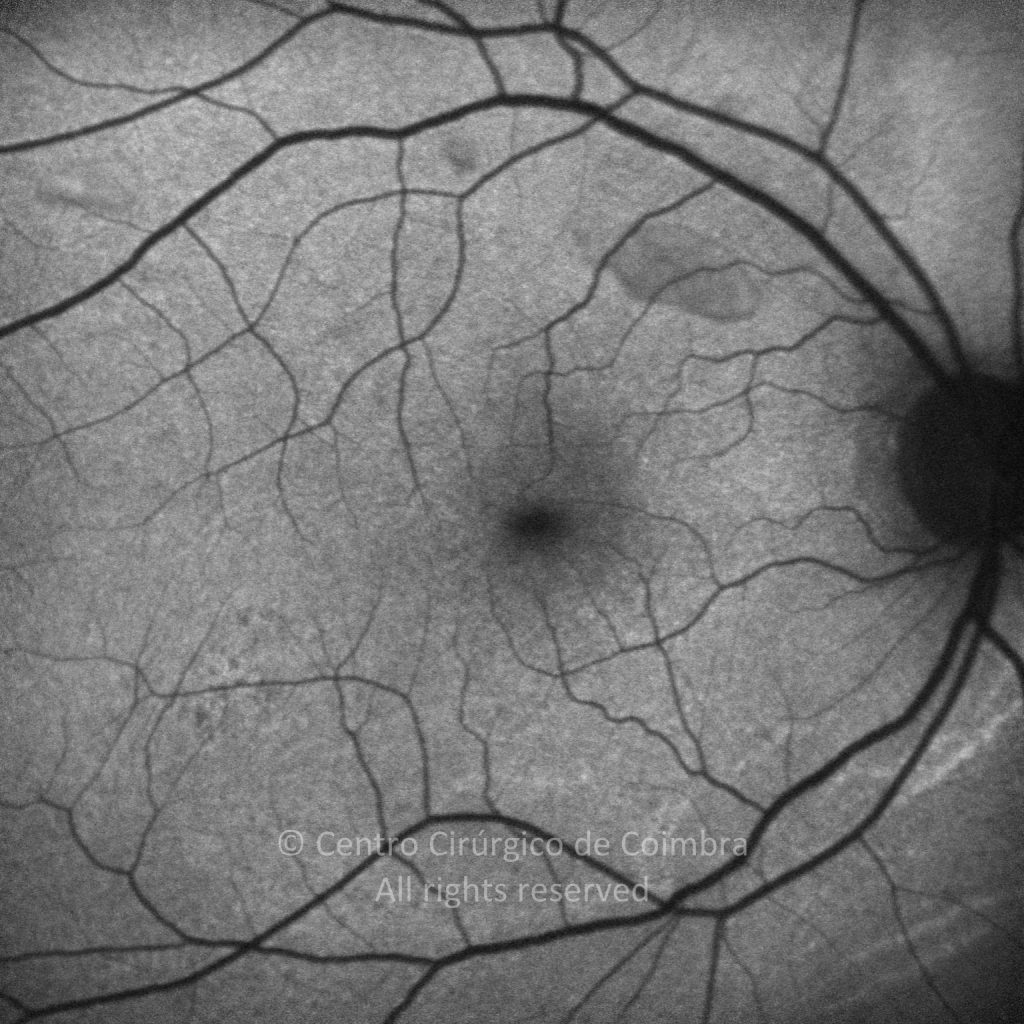

Paciente de 37 años con traumatismo contundente y ruptura del globo ocular. Presenta ruptura esclero-uveal, hifema, hemovítreo, desgarro periférico y temporal de la retina, hemorragias subretinianas y múltiples desprendimientos serosos.

MAVC: 20/25 OD, nueve años después de las cirugías (sutura escleral de la desinserción del músculo recto externo, vitrectomía posterior y fotocoagulación láser en el borde del desgarro retiniano, desprendimiento de retina inferior con proliferación vitreorretiniana y líquido subretiniano con algo de sangre; peeling de la membrana epirretiniana y maculorrexis de la MLI).